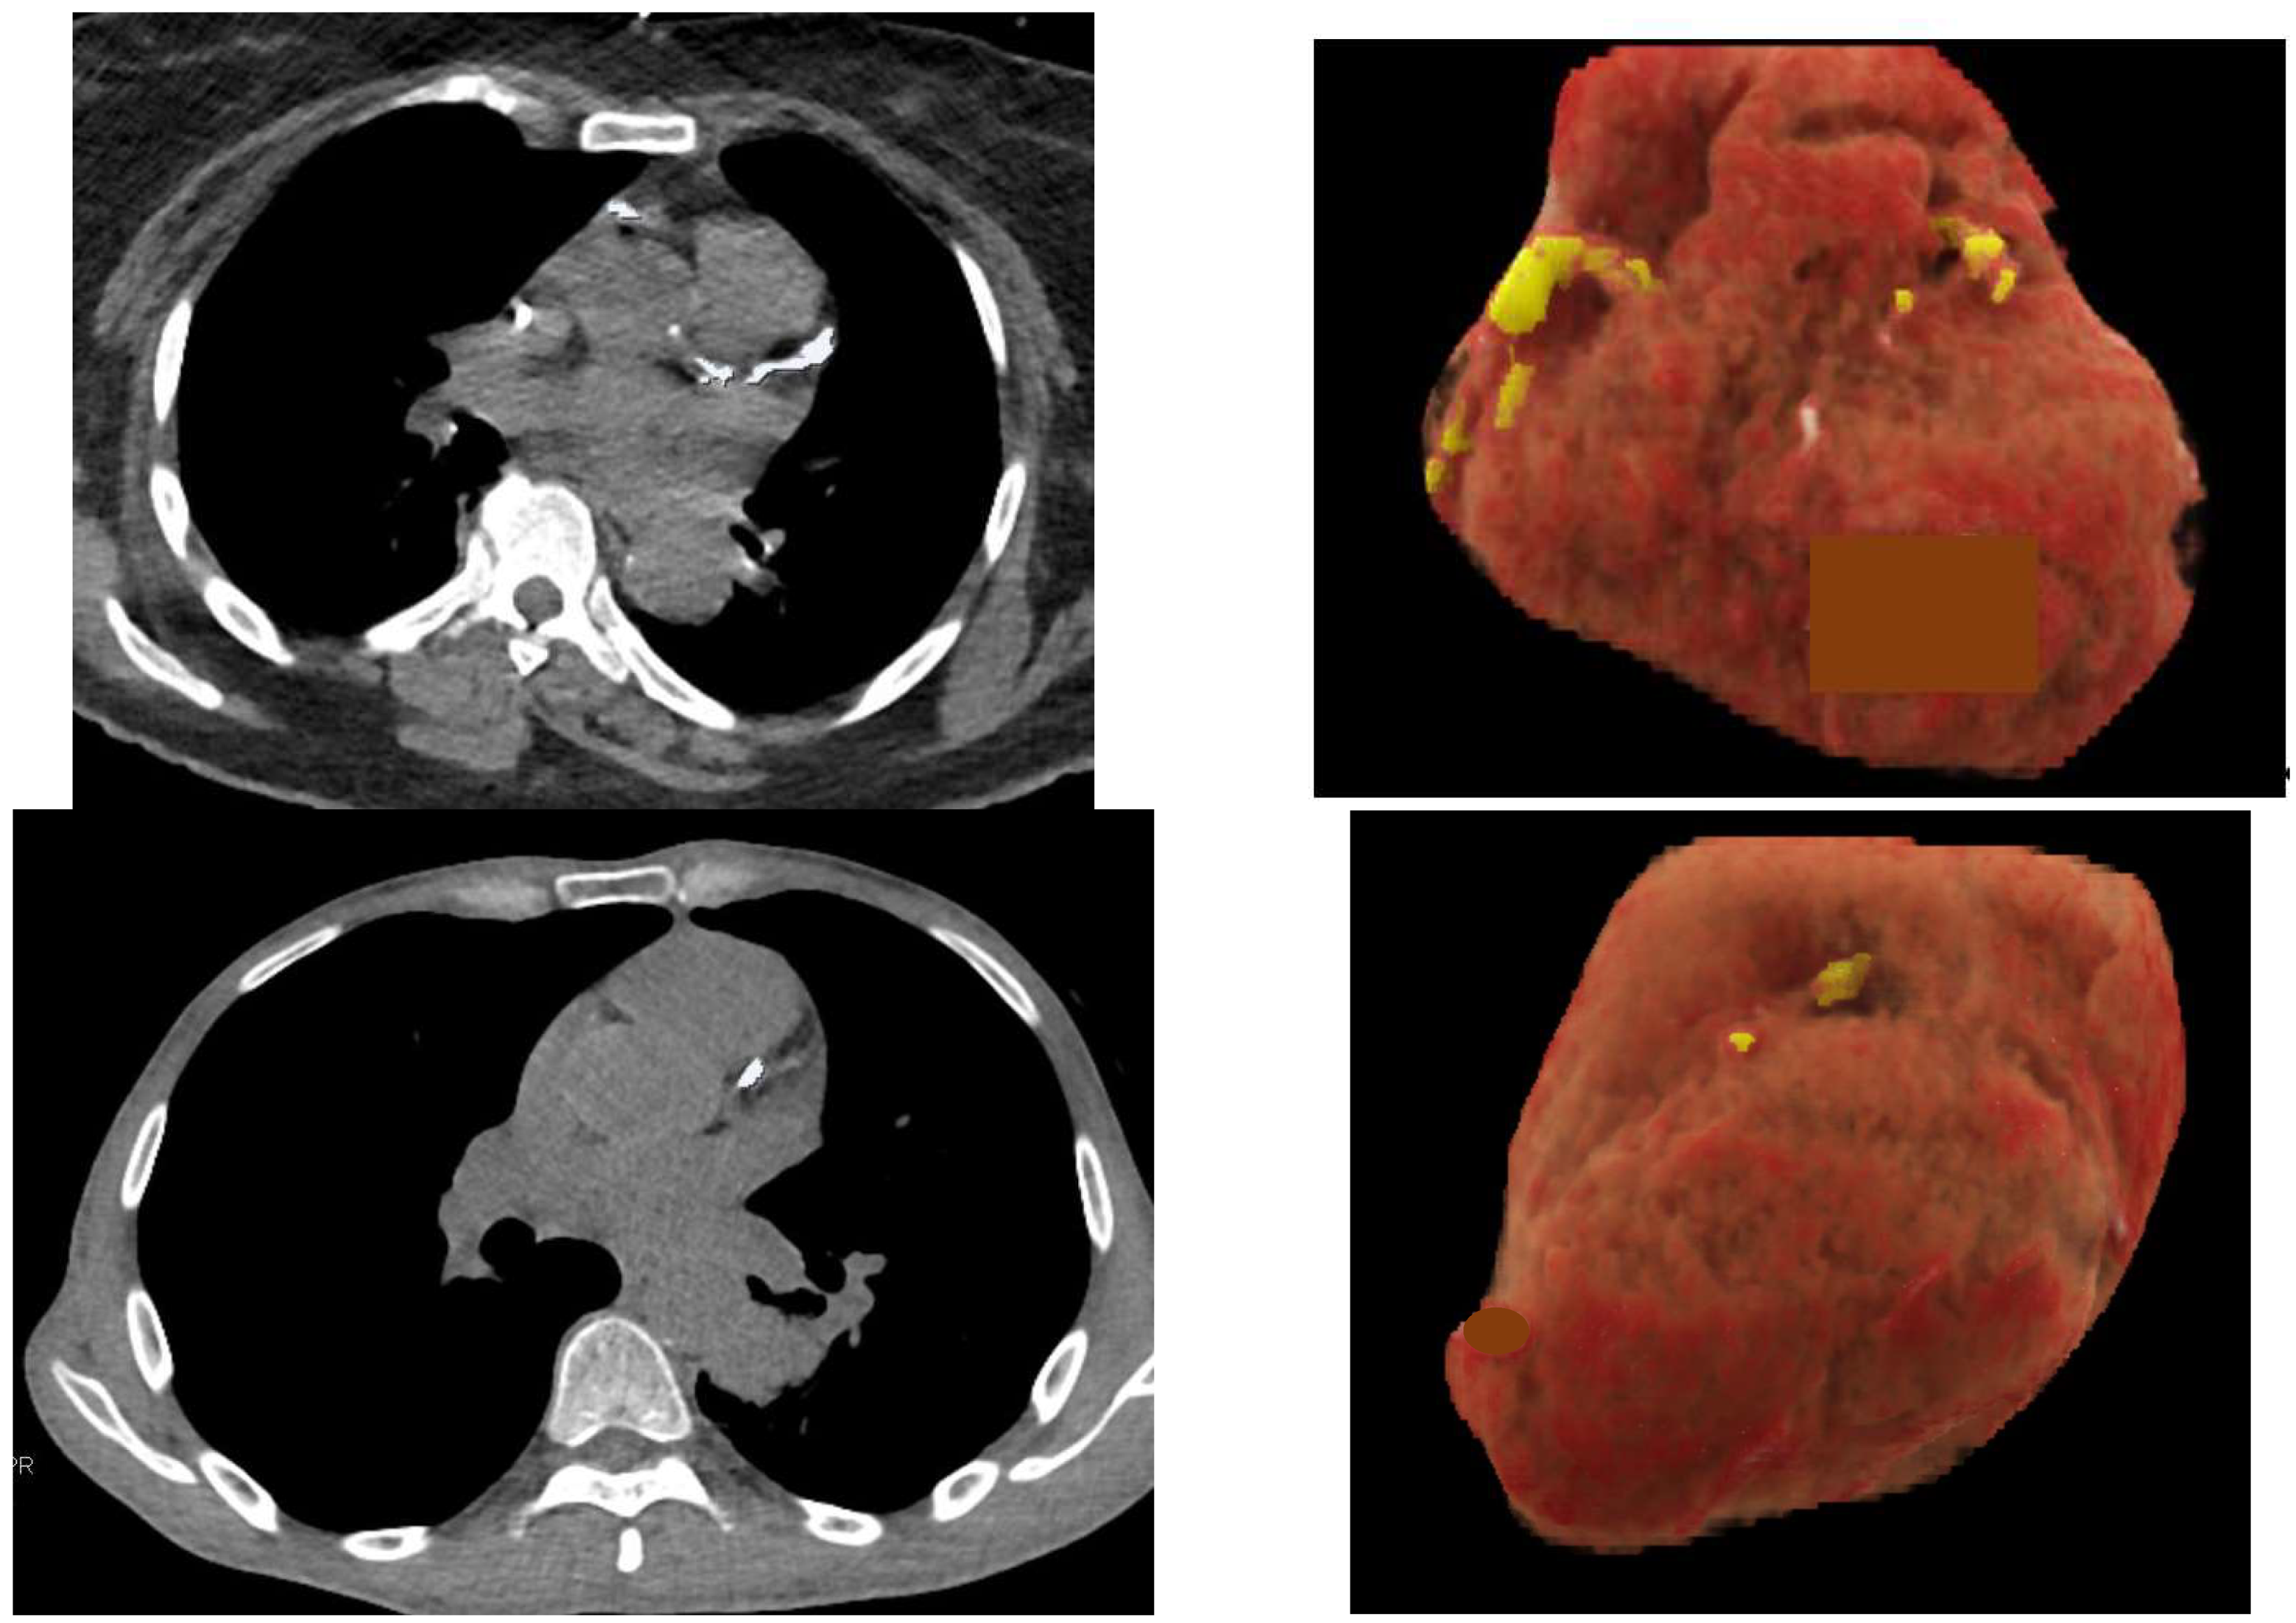

3.1. Coronary Artery Calcification and Cardiovascular Events

- Van Velzen, S.G.M.; Lessmann, N.; Velthuis, B.K.; Bank, I.E.M.; van den Bongard, D.H.J.G.; Leiner, T.; de Jong, P.A.; Veldhuis, W.B.; Correa, A.; Terry, J.G.; et al. Deep Learning for Automatic Calcium Scoring in CT: Validation Using Multiple Cardiac CT and Chest CT Protocols. Radiology 2020, 295, 66–79. [Google Scholar] [CrossRef]

- Chao, H.; Shan, H.; Homayounieh, F.; Singh, R.; Khera, R.D.; Guo, H.; Su, T.; Wang, G.; Kalra, M.K.; Yan, P. Deep learning predicts cardiovascular disease risks from lung cancer screening low dose computed tomography. Nat. Commun. 2021, 12, 2963. [Google Scholar] [CrossRef] [PubMed]